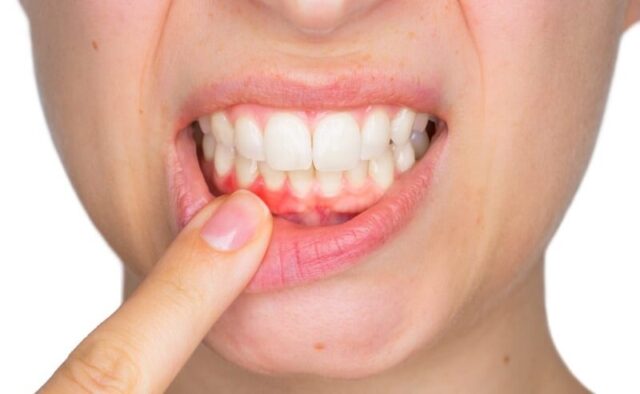

Biểu hiện: sưng lợi, chảy máu chân răng, hơi thở có mùi

Các biểu hiện của viêm quanh răng không quá khó để nhận biết nếu bạn chú ý quan sát. Thông thường, bệnh nhân sẽ cảm thấy lợi sưng đỏ, dễ chảy máu khi đánh răng hoặc dùng chỉ nha khoa. Hơi thở có mùi hôi là dấu hiệu rõ ràng minh chứng cho tình trạng viêm nhiễm trong khoang miệng.

Ngoài ra, răng có thể cảm giác lỏng lẻo hơn bình thường hoặc có cảm giác đau nhẹ khi ăn uống. Những triệu chứng này phản ánh tình trạng viêm đã diễn ra trong thời gian dài, cần được thăm khám và điều trị kịp thời để tránh các biến chứng nghiêm trọng hơn.